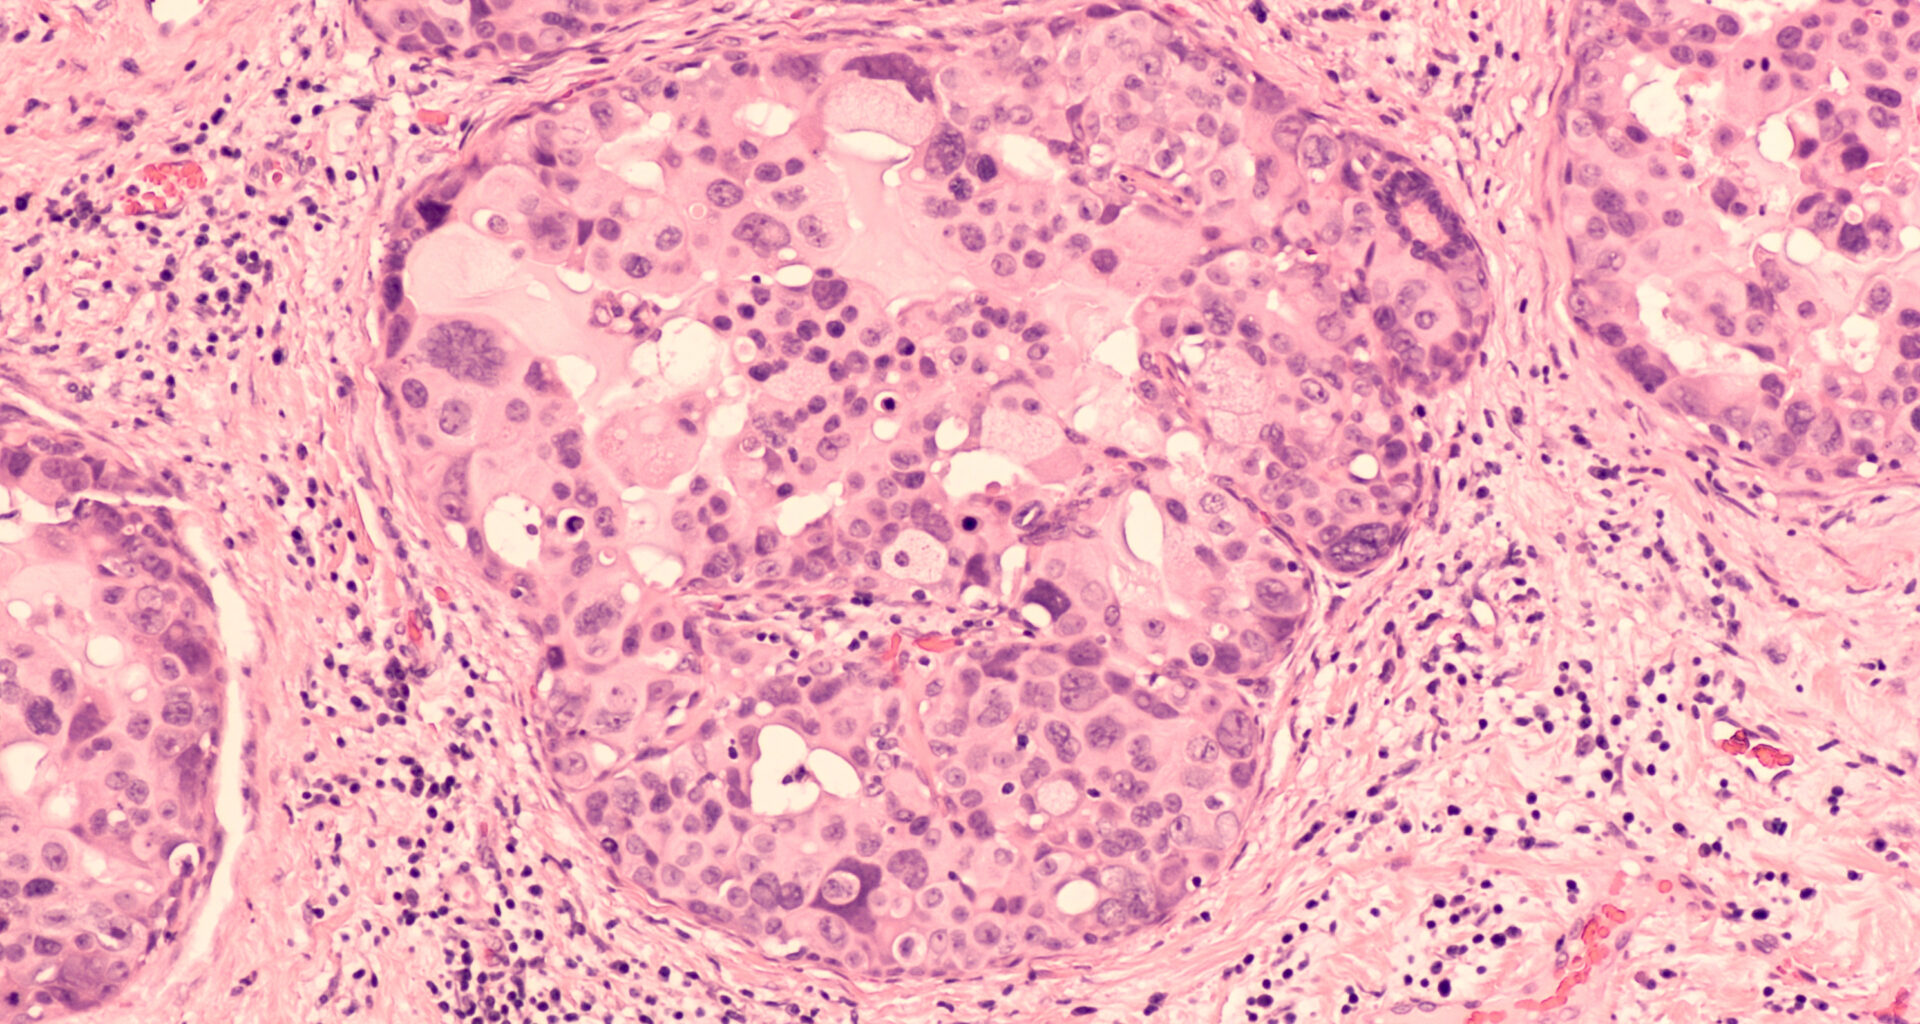

People diagnosed with DCIS have abnormal cells inside the milk ducts of their breast, but because these cells have not spread into the surrounding breast tissue, DCIS is not invasive breast cancer. DCIS can develop into invasive breast cancer over time, but research suggests that about four out of five cases will never become invasive or life-threatening. DCIS is typically treated with surgery and sometimes with radiotherapy or hormone therapy. Researchers launched the LORD trial (ClinicalTrials.gov identifier NCT02492607) to evaluate whether patients with low-risk DCIS can be safely monitored with regular check-ups instead of having immediate surgery.